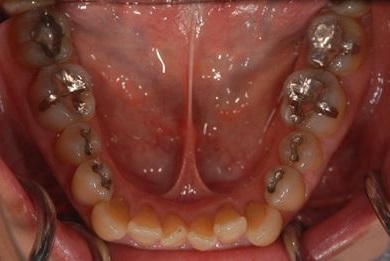

セラミックの症例写真 SHINBI

セラミック治療+ラミネートベニア治療

| 治療内容 | ジルコニアオールセラミッククラウン1本(オールセラミック用土台1本)、オールセラミッククラウン9本(オールセラミック用土台1本)、オールセラミックラミネートベニア11本 | ||||||||||||||||||||||||||||||||